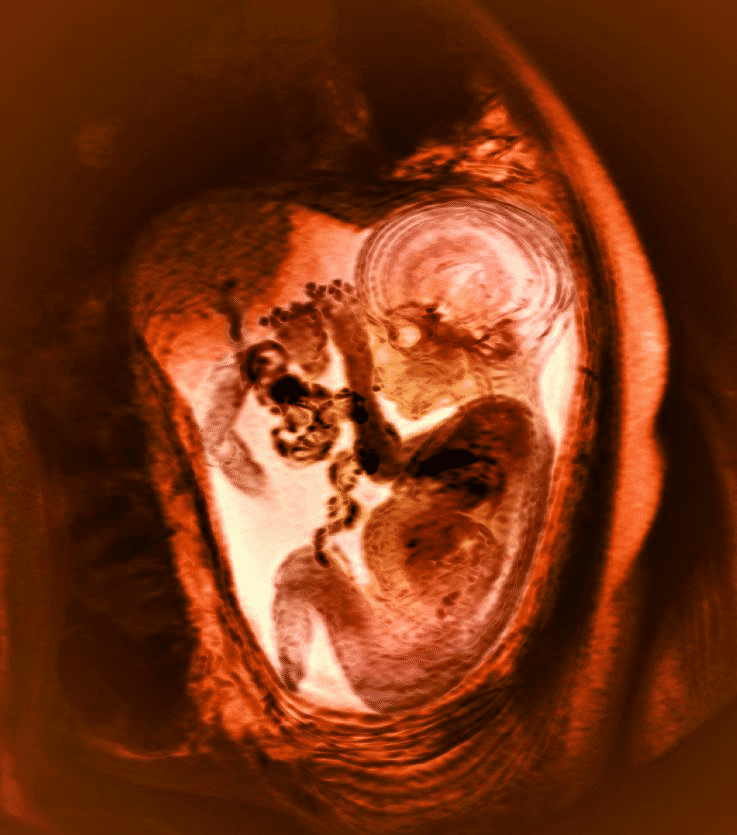

36 week foetus, MRI scan – Stock Image – P680/0551 – Science Photo Library